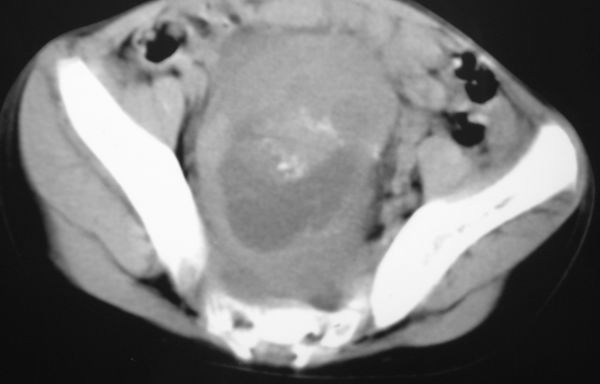

标题: PED0321:F 7 骶尾部肿瘤 有病理结果 [打印本页]

标题: PED0321:F 7 骶尾部肿瘤 有病理结果

骶尾部肿瘤 有病理结果

考虑畸胎瘤可能性大。骶尾骨无破坏。不考虑脊索瘤。

骶骨没有发现骨质破坏,畸胎瘤的可能性大